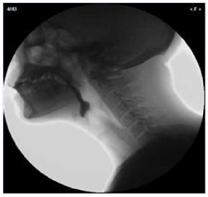

在吞咽和語言治療上,惠州三院語言(吞咽)治療部在惠州地區(qū)多次率先引進國內(nèi)先進治療技術(shù),如使用經(jīng)顱直流電直接對腦部不同功能區(qū)進行電刺激治療,對認知障礙、吞咽障礙、失語癥等均有較好的療效;2012年開展了吞咽造影技術(shù)、球囊擴張技術(shù),對吞咽障礙患者進行綜合治療,并取得顯著療效。

目前,語言(吞咽)治療部擁有領(lǐng)先的治療技術(shù):吞咽造影檢查技術(shù)、導尿管球囊擴張術(shù)、OPT口部肌肉定位治療技術(shù)、直流感應電刺激舌肌技術(shù)等。

▲吞咽造影檢查